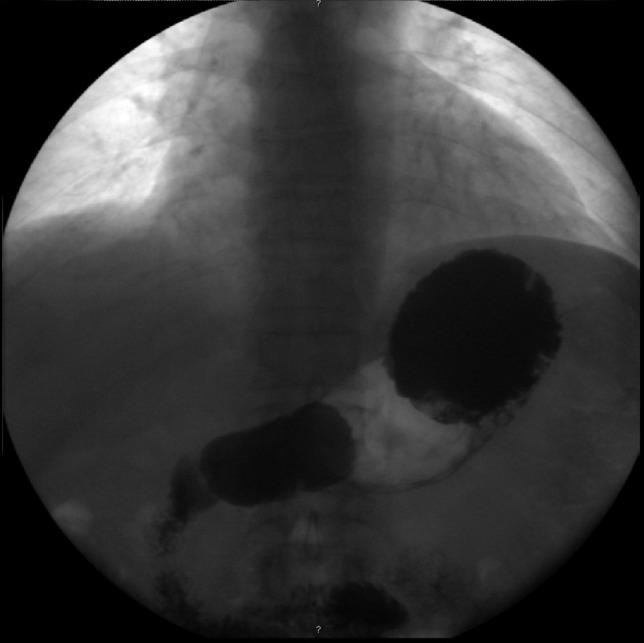

原发性胃扭转:两例报告。

Primary gastric volvulus: a report of two cases.

Gastric volvulus is an uncommon cause of gastric obstruction. It can be classified as primary when no underlying condition is identified as the cause for the rotation. An acute presentation includes typical symptoms and is frequently detected by imaging studies. Chronic cases present with intermittent vague symptoms and imaging studies may be normal during the symptomatic interval. The lack of specific symptoms and signs delays the diagnosis of chronic volvulus. However, appropriate treatment demands prompt diagnosis. We report two cases of primary gastric volvulus, with chronic or subacute symptoms and normal imaging studies during the asymptomatic periods. Both were treated surgically and had an uneventful follow-up.

摘要

胃扭转是胃梗阻的一种罕见原因。当未发现潜在病因导致胃扭转时,可将其归类为原发性。急性表现包括典型症状,常通过影像学检查发现。慢性病例表现为间歇性模糊症状,在症状发作期间影像学检查可能正常。缺乏特异性症状和体征会延迟慢性胃扭转的诊断。然而,恰当的治疗需要及时诊断。我们报告两例原发性胃扭转病例,均有慢性或亚急性症状,且在无症状期影像学检查正常。两例均接受了手术治疗,术后随访情况良好。